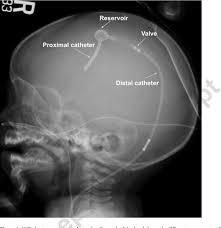

A Radiograph Of The Head With The Course Of The Vp Shunt Indicated By Download Scientific Diagram

Vp shunt valve x ray. Most pediatric patients with hydrocephalus are treated with ventriculoperitoneal vp shunt placement. Programmable cerebrospinal shunts are a type of ventriculoperitoneal shunt that can be set to different csf pressure settings. Usually a simple lateral skull x ray helps to identify the type of valve and it s adjustment.

Delay the shunt procedure when infections such as meningitis ventriculitis. This can be accomplished by aligning the proximal and distal connectors of the x ray image. Valves not fixed in the subcutaneous tissue pose a high risk to migrate into the distal site or retrograde into ventricles.

They are of particular value in normal pressure hydrocephalus and in pediatric patients. Shunt pass is not always at hand and documents from external hospitals can be missing. 1 provides radiographic features with reference images of the settings of five common valves codman hakim programmable valve medtronic.

The purpose of this study is to provide a single reference for the identification of programmable shunt valves and the interpretation of programmable shunt valve settings. Reviewed 2016 amr. Align red centerline of valve on overlay with the centerline of the valve x ray under review.